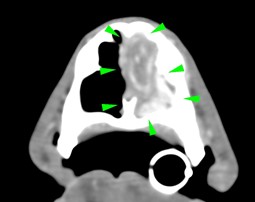

Diagnostic imaging is a pivotal part of the diagnostic process, narrowing down the likely causes of disease and allowing clinicians to understand the best way forward in achieving a definitive diagnosis and treatment plan.

Whether it’s assessment of acute or chronic disease including staging of cancer patients, or pre-surgical evaluation, the work of the team is crucial. Our expert team investigate all manner of conditions affecting any part or system of the body, from the bones to the brain.

Imaging is frequently used to guide biopsies of diseased organs that are otherwise inaccessible, or to find and retrieve foreign bodies. Both applications are extremely useful and can avoid the need for more invasive surgery.